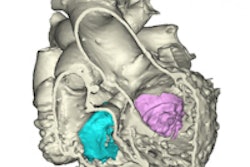

Greater use of 3D printing technology in hospitals would reduce the duration of surgery, anesthesia exposure, and operative risks; aid in effective presurgical planning; and improve surgical practice, according to Allied Market Research. 3D-printed organs have also provided alternative methods for animal testing, assisting the market growth by shortening the time span for clinical trials and reducing cost and risks associated with testing new drugs, the company said.